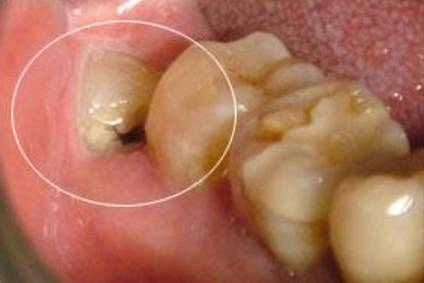

是智齿冠周炎么,脸颊有点小肿,牙冠长出来一半,还有一半在牙龈包裹着

通俗来说,就是我们的智齿长了一点没长出来完全,或者在牙龈下面横起长